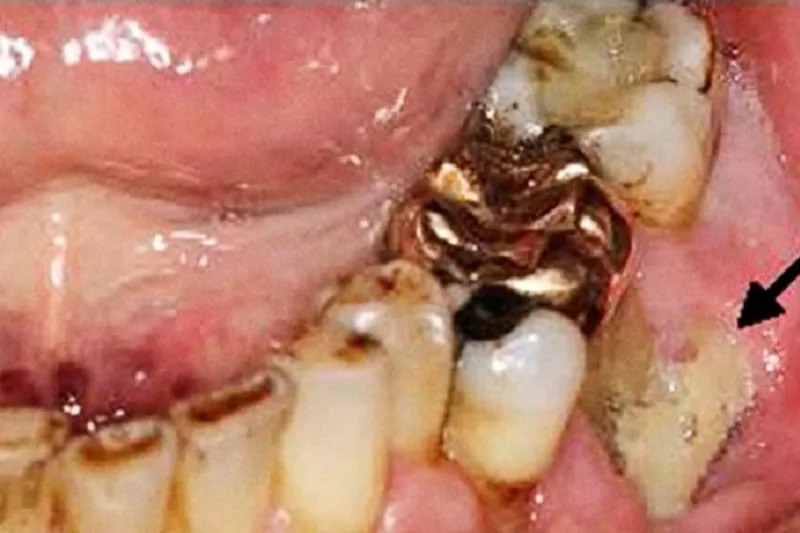

Medicinsk induceret osteonekrose i kæberne (MRONJ) grundet lavdosis knoglestyrkende behandling (LKB) er et velkendt problem i primær- og sekundærsektoren.

Risikoen for udvikling af MRONJ er afhængig af dosis, behandlingsperiode, præparat samt lokale og generelle risikofaktorer.

Hyppigste årsag til MRONJ er tandekstraktioner (53,2 %).